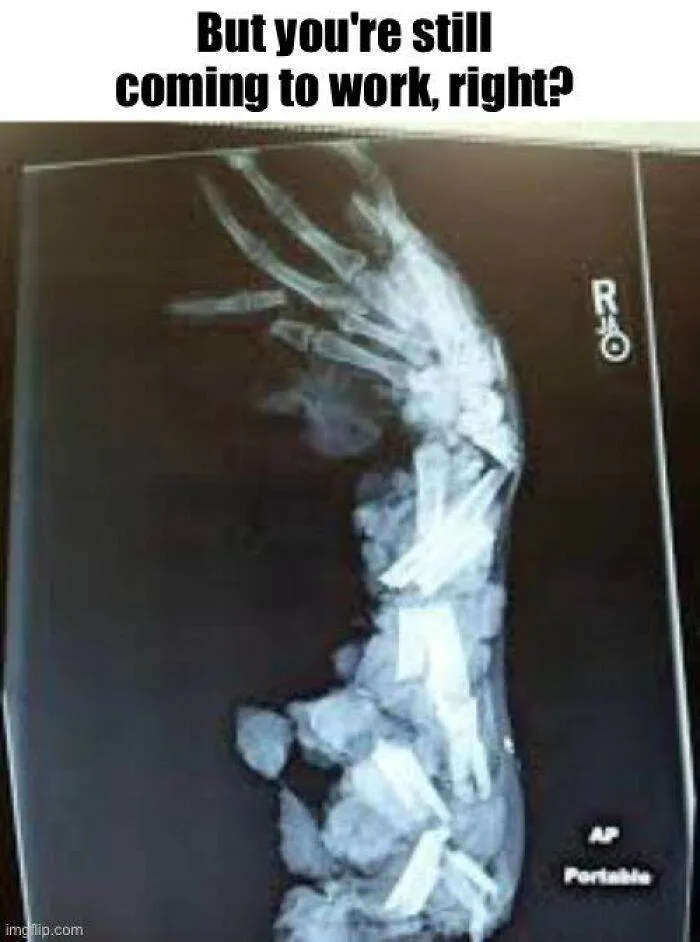

oh no